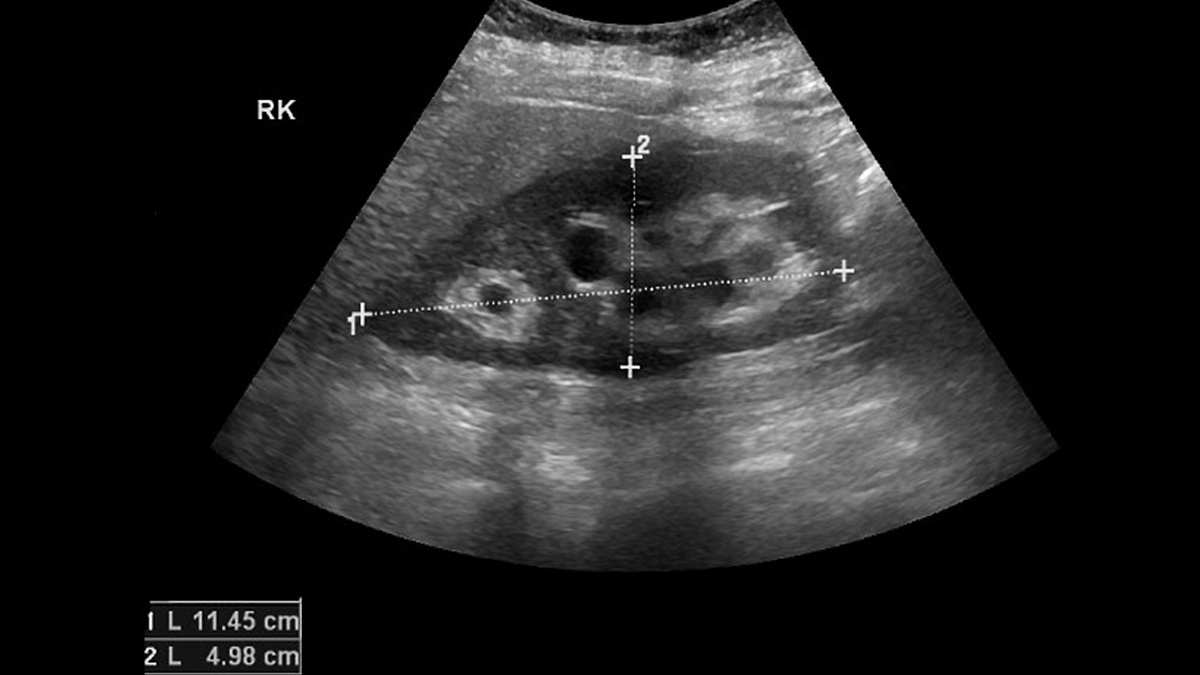

इसकी असामान्य घटना को देखते हुए, गर्भाशय ग्रीवा के लिंफोमा का निदान करने में अक्सर चिकित्सा इमेजिंग, बायोप्सी और रोग संबंधी मूल्यांकन का संयोजन शामिल होता है। डॉ. शेट्टी ने बताया कि प्रक्रिया आमतौर पर पैल्विक परीक्षा से शुरू होती है, जहाँ गर्भाशय ग्रीवा में कोई भी असामान्यता अल्ट्रासाउंड, एमआरआई या सीटी स्कैन जैसे इमेजिंग परीक्षणों के माध्यम से आगे की जांच को प्रेरित कर सकती है।

निदान की पुष्टि के लिए गर्भाशय ग्रीवा के ऊतकों की बायोप्सी महत्वपूर्ण है। पैथोलॉजिस्ट लिम्फोइड कोशिकाओं की उपस्थिति की पहचान करने और लिम्फोमा के विशिष्ट प्रकार को निर्धारित करने के लिए माइक्रोस्कोप के नीचे ऊतक की जांच करते हैं। कैंसर के चरण को स्थापित करने के लिए, अतिरिक्त इमेजिंग और संभवतः अस्थि मज्जा बायोप्सी आयोजित की जा सकती है, जो उपचार योजना को तैयार करने में मदद करती है।